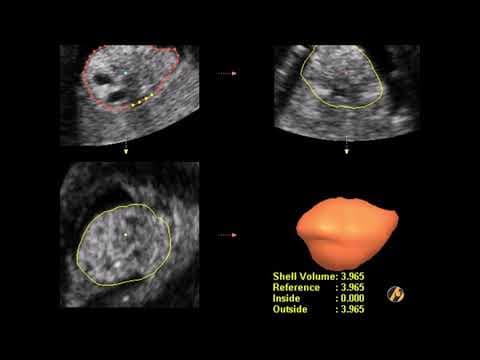

- 3D/4D/5D ultrazvuk i fetalna medicina

• 2D ultrazvuk = standardna ravna slika (sve poliklinike imaju) • 3D ultrazvuk = trodimenzionalna slika fetusa (detaljnije vide se anomalije) • 4D ultrazvuk = 3D slika u pokretu (vidite fetus kako se mijenja u realnom vremenu) • 5D/HD Live ultrazvuk = najnaprednija tehnologija s detaljima kao fotografija U Poliklinici Harni koristimo 3D, 4D i 5D ultrazvuk, što nam omogućava ranom otkrivanju anomalija i pružanju roditeljima jasne slike bebe prije poroda.